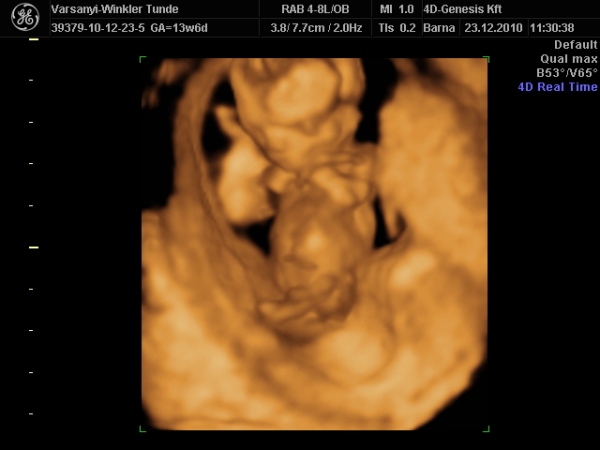

)2010.12.23 11:37